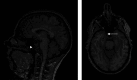

ABSTRACTAmong healthy volunteers in psychiatric brain functional magnetic resonance imaging (fMRI) research studies, the prevalence of incidentalomas can be as high as 34%, of which 10% show clinical significance. An incidentaloma is a lesion found by coincidence without clinical symptoms or suspicion. Like lesions and other types of accidental findings, it is found in healthy individuals recruited to take part in psychiatric studies. The prevalence of these accidental findings among specific psychiatric populations remains unknown. However, a precise understanding of cerebral neuroanatomy, neuroradiological expertise, and an appropriate choice of fMRI exploration sequences will increase the sensitivity of identifying these accidental findings and enable researchers to address their clinical relevance and nature. We present recommendations on how to appropriately inform patients or participants of the accidental findings. Additionally, we propose specific suggestions pertaining to the clinical research setting aimed for investigators and psychiatrists. Unlike current articles pertaining to incidentaloma, the current report provides a distinct focus on psychiatric issues and specific recommendations for studies involving psychiatric patients.